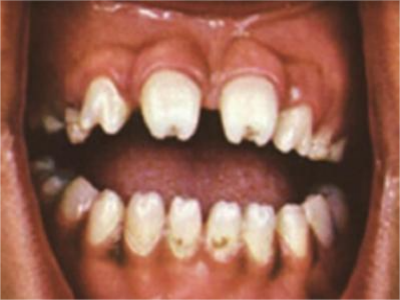

先天性梅毒牙主要表现为半月形切牙以及桑葚状磨牙,具体表现如下:

1、半月形切牙:上中切牙及下中切牙切缘较牙冠中部窄,中央部有切迹,两切角圆钝,有如新月形,因牙齿形态变化,使牙间空隙增大。

2、桑葚状磨牙:第一恒磨牙(牙合)面缩小,牙尖萎缩,呈发育不良的结节状压挤在一起,釉质呈小颗粒状或坑窝状凹陷,似桑葚样。牙冠短小,牙尖向中央聚拢而颈部周径大,牙齿可呈暗褐色。